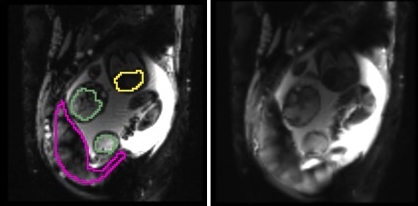

Case 1 Case 2

, manual , manual

, manual , automatic , manual , automatic

(a) Placentae

(b) Fetal brains

(c) Fetal livers

Fig. 2 illustrates results for two example cases from the study. We observe that the reference frame was warped accurately by the algorithm to represent a frame in the series that is substantially different in the regions of the placenta and the fetal liver. The delineations achieved by transferring manual segmentations from the reference frame to the coordinate system of the current frame ( in the figure) are in good alignment with the manual segmentations for the current frame. Fig. 3 reports volume overlap statistics for the placentae, fetal brains, and fetal livers, for each case in the study. We observe that temporal alignment improves volume overlap in important ROIs and offers consistent improvement for all cases over pairwise registration to the reference frame. We also note that temporal alignment offers particularly substantial gains in cases with a lot of motion, i.e., low original volume overlap.